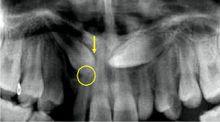

李蓓,段銀鍾,劉嵐.阻生上頜尖牙曲斷片影像學指標與治療預後的相關性.醫學爭鳴.LI Bei,DUAN Yin Zhong,LIU Lan.Correlation between panoramic radiographic findings and prognosis of impacted maxillary canines.2007,23:2166-2168.

李蓓.全口曲面斷層片在上頜阻生尖牙診治過程中的套用研究.第四軍醫大學.

李蓓發表的醫學論著圖李蓓,王冉,閆黎津,常平,魯莉英.曲面斷層片診斷阻生上頜尖牙造成的切牙牙根吸收的有效性研究.口腔頜面修復學雜誌,Chinese Journal of Prosthodontics.2009,05:269-271.